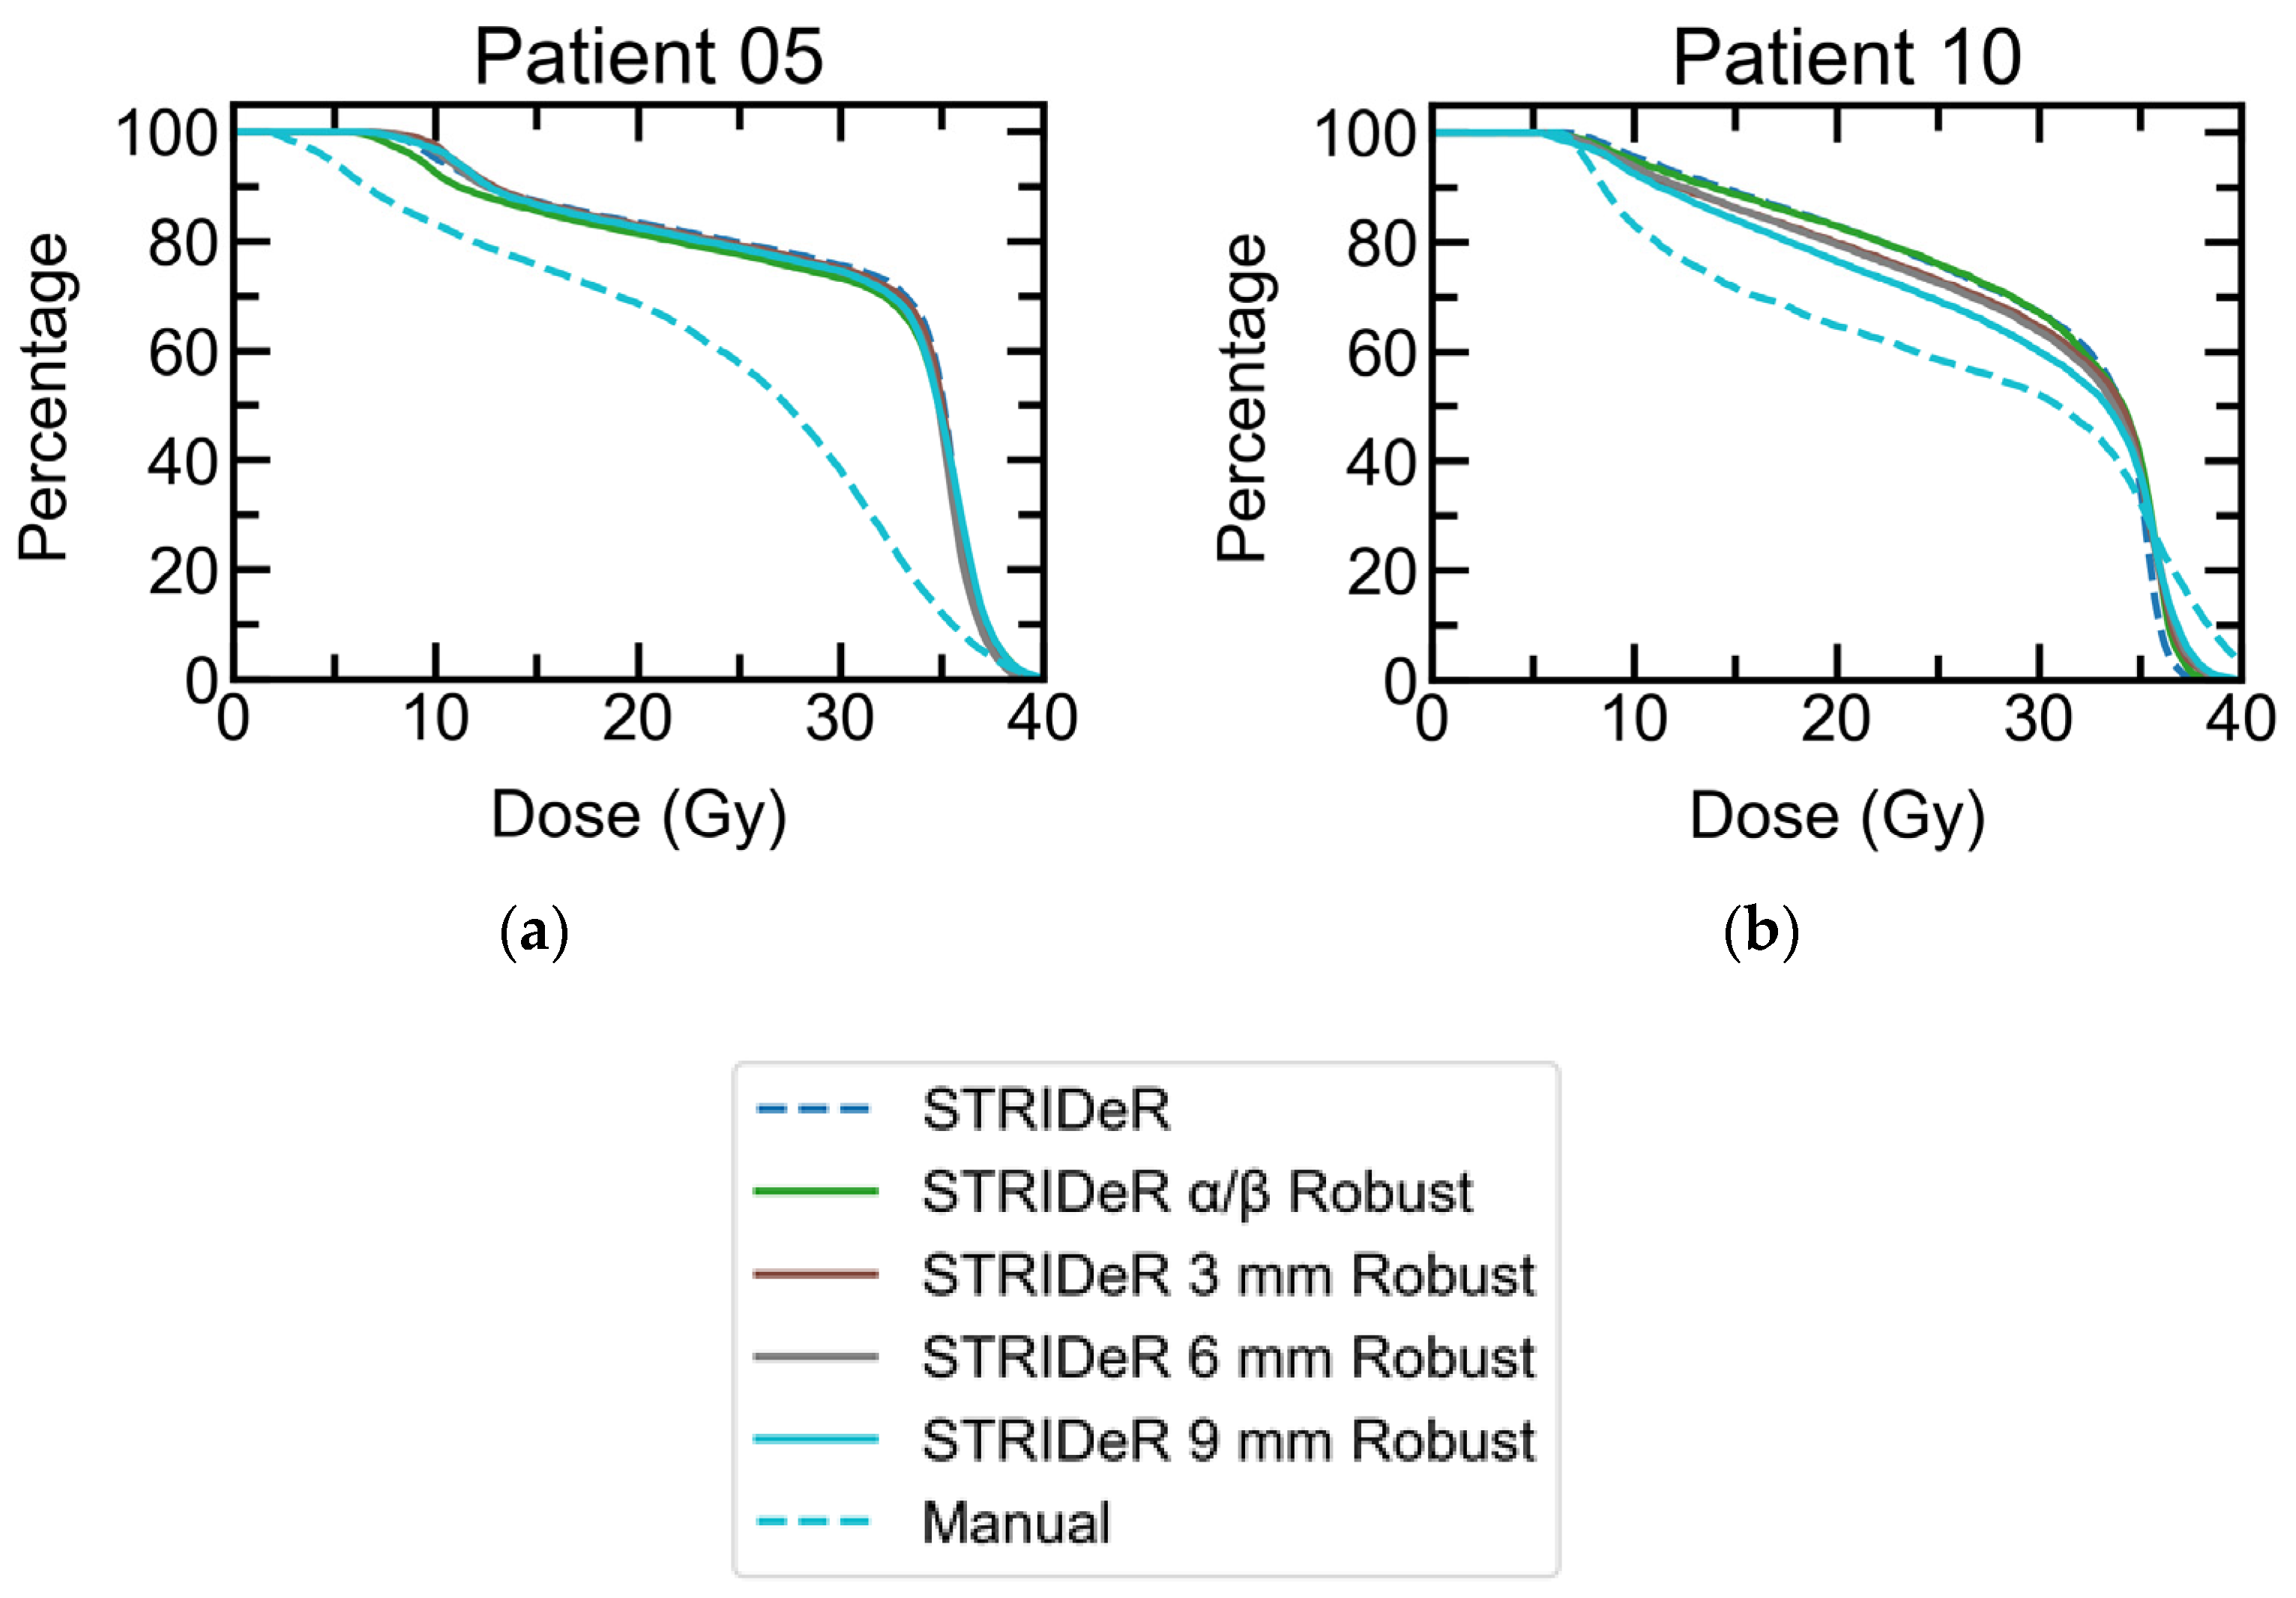

3.1. Baseline Plans

3.2. Robustness

3.2.1. Geometric Robustness

3.2.2. Fractionation Sensitivity

3.2.3. LQ Model Robustness